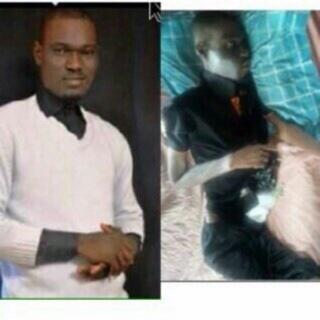

Dauda Oriyomi Yusuf is battling cancer of the blood and currently on admission at the University College Hospital Ibadan. He needs our help to pay for his treatment. Please donate to Dauda Oriyomi Yusuf / 3101703319 / First Bank of Nigeria Donate & Share please 🙏 #SaveYusuf

Alhamdulillah We have raised: ₦2,758,900 Pending fund: ₦4,741,100 Goal: ₦7,500,000 Updated On: 1/10/2023 Days Left to raise funds: 19 days Please, nothing is too little to help him get his life back. #saveyusuf Account Number: 9626880922 Bank Name: Providus Bank Account…

He was diagnosed with anterior mitral valve prolapse with severe mitral regurgitation, dilated right ventricle, pulmonary hypertension, and persistent left superior/vena cava, which has seen him wreaking havoc with pain and running from pillar to pole to raise the funds

Alhamdulillah for the progress so far. We have raised: ₦256,100 Shortfall: ₦7,243,900 Goal: ₦7,500,000 Please help #saveyusuf Bank Name: Providus Acc Number: 9626880922 Acc Name: Help Save Yusuf Donate Anonymously Via: mosquepay.org/yusuf Checkout our story…

He was diagnosed with anterior mitral valve prolapse with severe mitral regurgitation, dilated right ventricle, pulmonary hypertension, and persistent left superior/vena cava, which has seen him wreaking havoc with pain and running from pillar to pole to raise the funds

Alhamdulillah We have raised: ₦2,758,900 Pending fund: ₦4,741,100 Goal: ₦7,500,000 Updated On: 1/10/2023 Days Left to raise funds: 19 days Please, nothing is too little to help him get his life back. #saveyusuf Account Number: 9626880922 Bank Name: Providus Bank Account…

He was diagnosed with anterior mitral valve prolapse with severe mitral regurgitation, dilated right ventricle, pulmonary hypertension, and persistent left superior/vena cava, which has seen him wreaking havoc with pain and running from pillar to pole to raise the funds

Alhamdulillah We have raised: ₦2,163,791 Pending fund: ₦5,336,209 Goal: ₦7,500,000 Please, nothing is too little to help him get his life back. Account Number: 9626880922 Bank Name: Providus Bank Account Name: Help Save Yusuf Donation link: mosquepay.org/yusuf #saveyusuf

Alhamdulillah for the progress so far. We have raised: ₦256,100 Shortfall: ₦7,243,900 Goal: ₦7,500,000 Please help #saveyusuf Bank Name: Providus Acc Number: 9626880922 Acc Name: Help Save Yusuf Donate Anonymously Via: mosquepay.org/yusuf Checkout our story…

He was diagnosed with anterior mitral valve prolapse with severe mitral regurgitation, dilated right ventricle, pulmonary hypertension, and persistent left superior/vena cava, which has seen him wreaking havoc with pain and running from pillar to pole to raise the funds

Dauda Oriyomi Yusuf is battling cancer of the blood and currently on admission at the University College Hospital Ibadan. He needs our help to pay for his treatment. Please donate to Dauda Oriyomi Yusuf / 3101703319 / First Bank of Nigeria Donate & Share please 🙏 #SaveYusuf